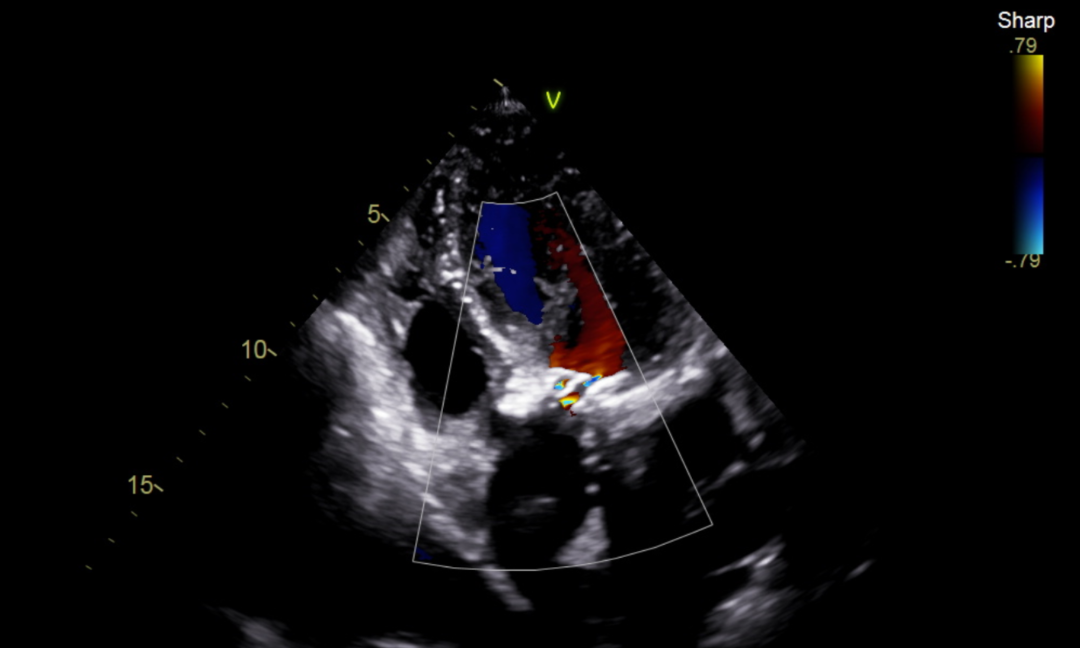

患者男性,78岁,术前心脏超声提示主动脉瓣重度狭窄伴轻度返流。CT评估结果显示三叶瓣,钙化均匀分布在三冠瓣,瓣环平均直径26.8mm,面积径25.7mm,左、右冠脉开口高度较高,无冠脉梗阻风险。下肢血管评估发现患者左侧髂外动脉瘤,下肢血管轻微钙化。